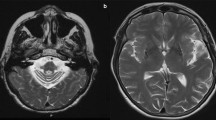

MRIs (ages 3 and 6 years) in patient 1 showed symmetric signal abnormalities in the cerebral white matter, with mild swelling and frontal predominance. Despite serious clinical deterioration and demise soon after the second MRI, the white matter abnormalities showed only minor increase (Fig. 1a, b). In patient 2, the initial MRI at the age of 2 years showed signal abnormalities in the periventricular and deep cerebral white matter without swelling and without frontal predominance. During a follow-up of 18 years, during which the patient clinically remained remarkably stable, the frontal white matter abnormalities showed some increase and became more marked than the parieto-occipital white matter abnormalities, although the cerebral white matter abnormalities remained limited in their extent in all areas. In patient 3, three MRI studies (ages 6–10 years) showed bilateral frontal white matter abnormalities with swelling (Fig. 1c, d). The only change regarding the white matter abnormalities over time was that the FLAIR images revealed a progressive decrease of signal intensity, indicating white matter rarefaction and cystic degeneration. During this time, the patient deteriorated seriously and died shortly after the third MRI. In patient 4, three MRI studies (4–8 years) demonstrated extensive cerebral white matter abnormalities with swelling and frontal preponderance. FLAIR images show evidence of white matter rarefaction and cystic change. Over time, the cerebral white matter signal abnormalities showed some increase in extent. The most marked change was progressive white matter atrophy with secondary dilatation of the lateral ventricles. This patient showed moderate clinical deterioration during this time. In patient 5, extensive areas of abnormal signal in the white matter were found on MRI at 6 years with a mild frontal predominance. Follow-up MRI after 2 years was unchanged. The patient was clinically stable. MRI in patient 6 revealed symmetric frontal white matter abnormalities almost restricted to the frontal and parietal lobes at 4 years. After 1 year, only some increase in white matter swelling was observed. This patient experienced serious clinical deterioration and died.

Transverse T2-weighted images (3,000/22, 60 and 120, one excitation) in two patients. MRIs at ages 3 (a) and 6 years (b) in patient 1 showed symmetric signal abnormalities in the cerebral white matter, with mild swelling and a frontal predominance. The white matter abnormalities showed only minor increase on follow-up. In patient 3, two MRI studies at age 8 (c) and 10 years (d) showed little change in the bilateral frontal white matter abnormalities with swelling